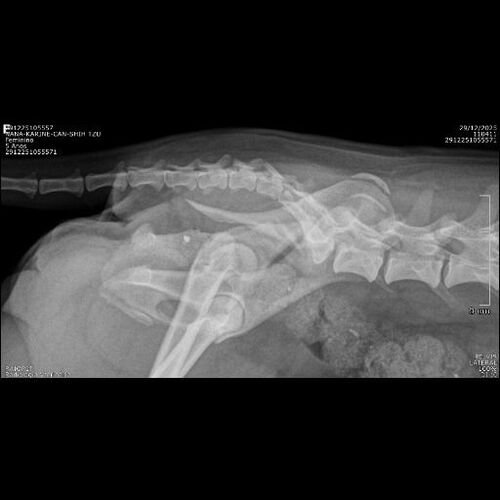

No dia 24, uma cadelinha foi atropelada na frente da nossa casa. Ao ver a situação, não conseguimos ignorar e imediatamente prestamos socorro, levando-a ao veterinário.

Desde então, ela está internada, recebendo cuidados, exames e medicação. Infelizmente, devido à gravidade do atropelamento, ela precisará passar por uma cirurgia ortopédica de quadril urgente para ter chance de recuperação e voltar a andar e viver sem dor.